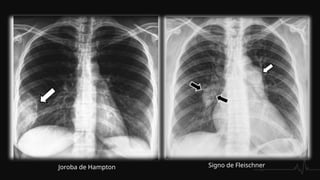

 Ensanchamiento de la silueta cardiomediastínica, debido al aumento del

calibre de las arterias centrales.

 Infarto pulmonar. Se observa un infiltrado alveolar localizado , en forma de

cuña, triangular y de base pleural, generalmente basal, con borde inferior

convexo (joroba de Hampton)

 Signos de Wetsermark: área de enfisema local causado por un defecto

en la perfusión que con leva una hiperclaridad marcada.

 Signo de Fleischner: dilatación de la arteria debido a la impactación del

émbolo.

 Atelectasias laminares basales con elevación del hemidiafragma

 Derrame pleural

Joroba de Hampton Signo de Fleischner

Signo de Westermark

RADIOGRAFÍA DE TORAX Ensanchamiento de la silueta cardiomediastínica, debido al aumento del calibre de las arterias centrales.  Infarto pulmonar. Se observa un infiltrado alveolar localizado , en forma de cuña, triangular y de base pleural, generalmente basal, con borde inferior convexo (joroba de Hampton)  Signos de Wetsermark: área de enfisema local causado por un defecto en la perfusión que con leva una hiperclaridad marcada.  Signo de Fleischner: dilatación de la arteria debido a la impactación del émbolo.  Atelectasias laminares basales con elevación del hemidiafragma  Derrame pleural

Joroba de HamptonSigno de Fleischner